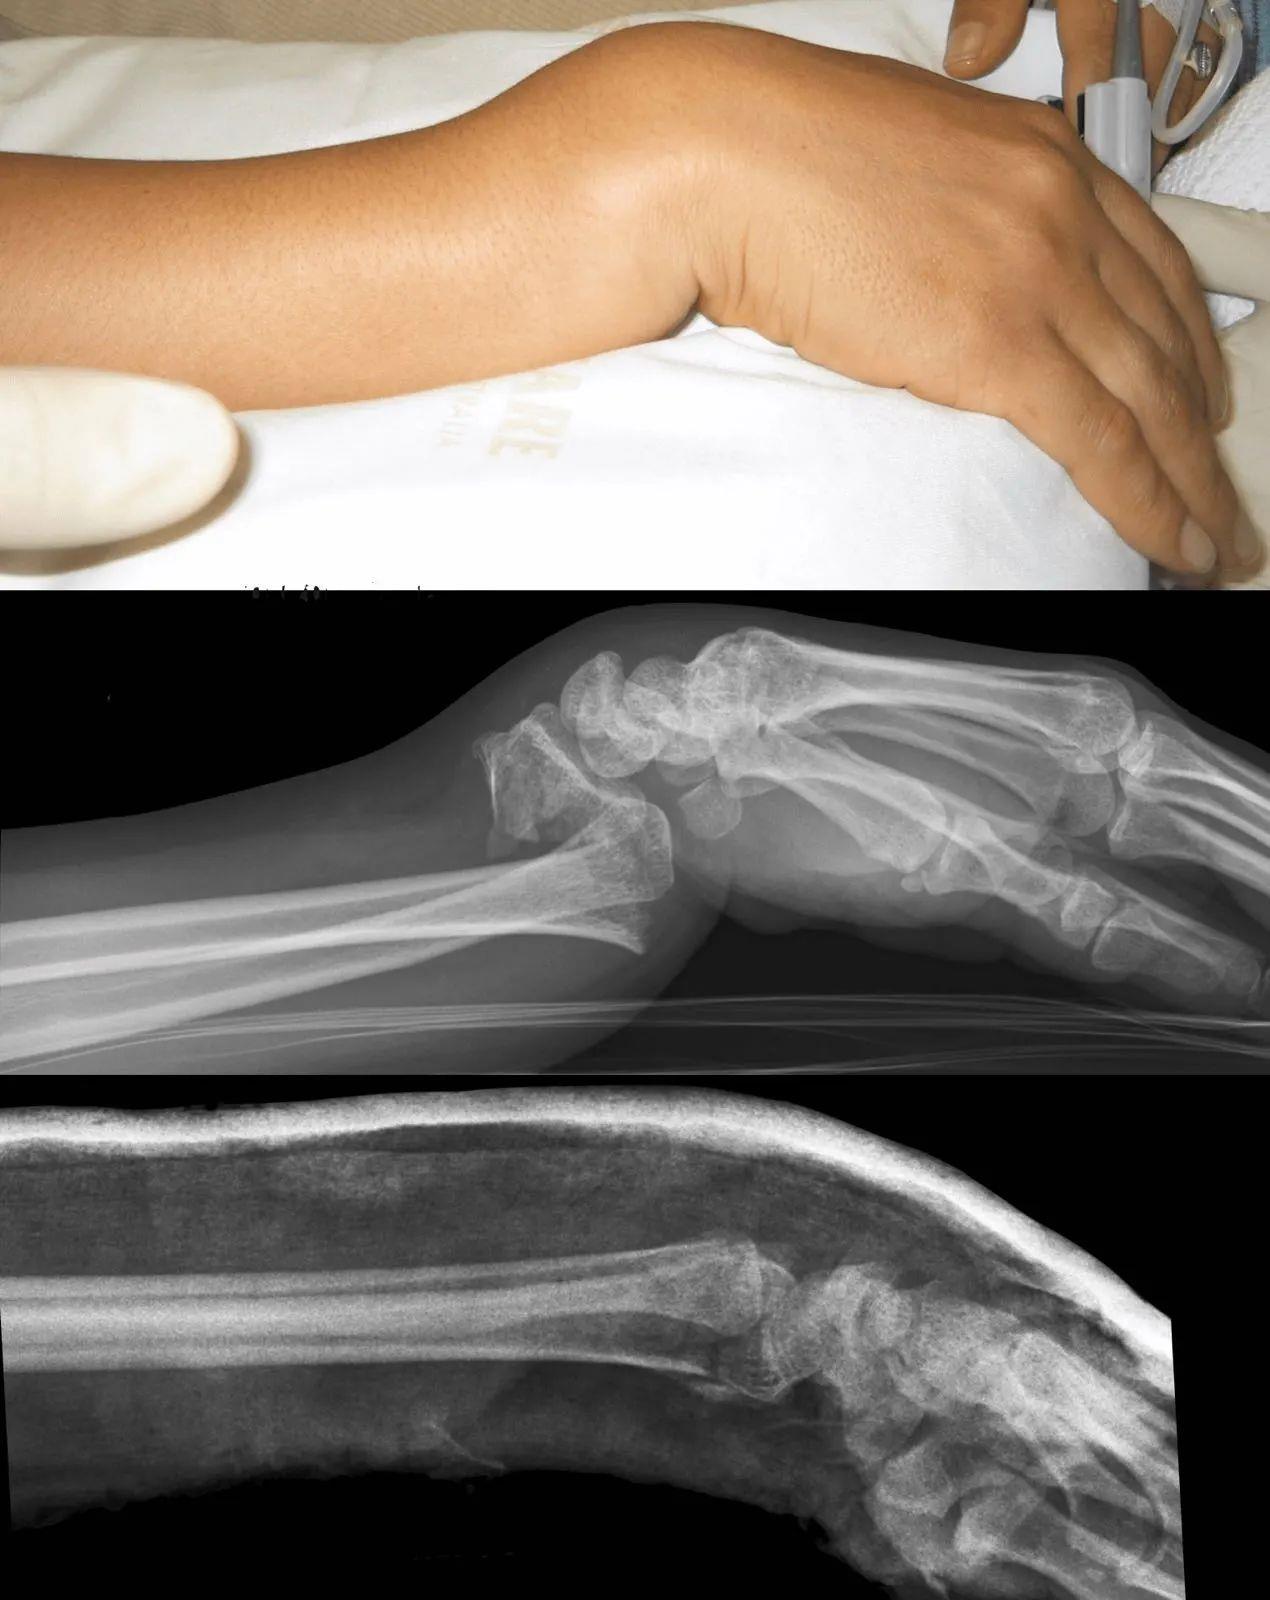

大家都知道,我们摔倒下意识反应就是手撑地。如果是年纪比较大的老人,本身就有一些骨质疏松,摔的时候身体协调能力又不是很好,这个时候他手着地往下一戳,如果是往后手背先着地,叫Smith骨折;手心着地就容易出现Colles骨折,出现餐叉样畸形。如果骨折复位后感觉比较稳定,打石膏固定一段时间就可以,个别情况可能还需要手术复位。